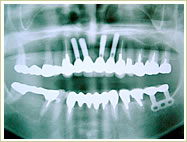

症例 65歳 男性 インプラント埋入数:11本 画像拡大

治療前 治療後